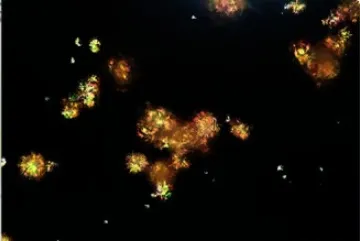

Uma causa incomum de hematúria glomerular intermitente!

Hematúria pós infecção, caso clínicos para auxiliar no entendimento de causas glomerulares comuns e raras...